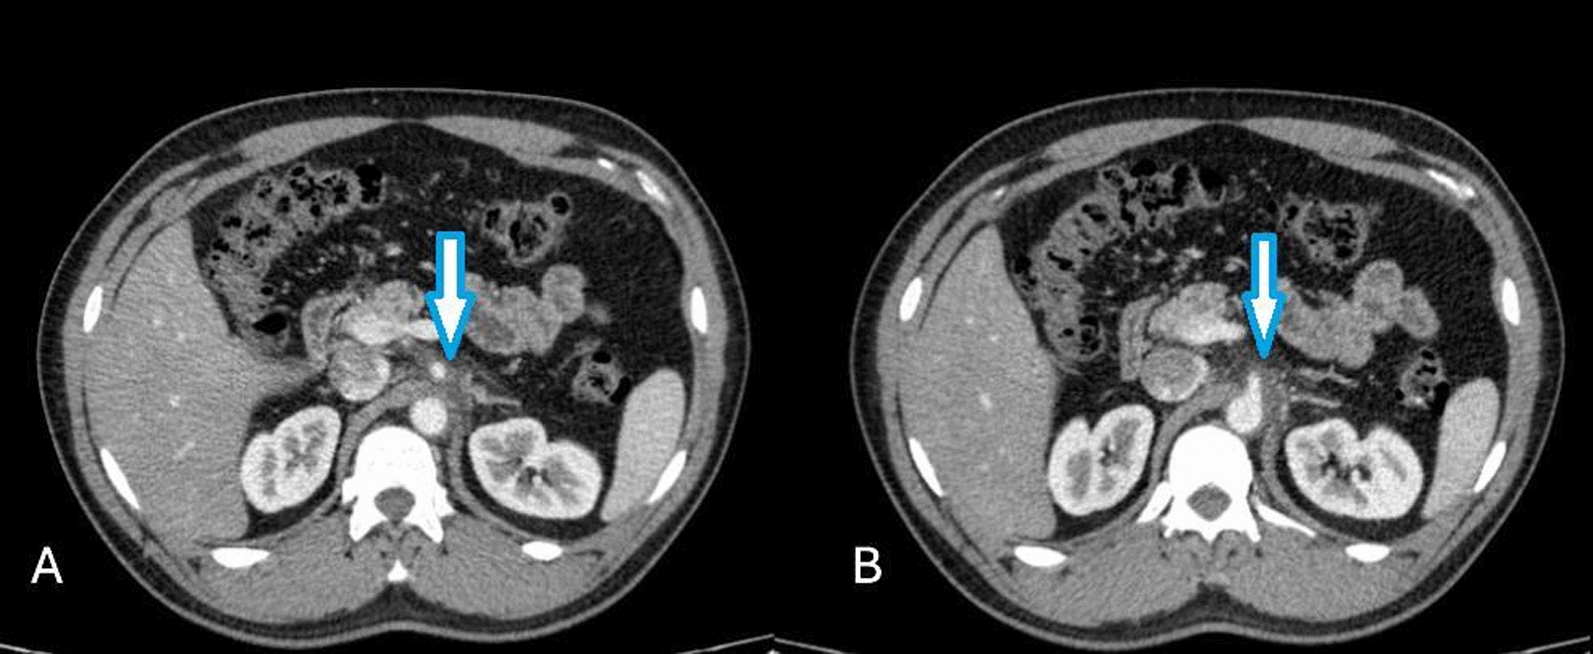

Fig. 2.

Contrast-enhanced abdominopelvic computed tomography scan in the axial plane (A, B) showing soft tissue density surrounding the origin and proximal portion of the celiac artery, resulting in minimal luminal narrowing (blue arrows). No evidence of aneurysm or dilation is observed along the course of the celiac artery